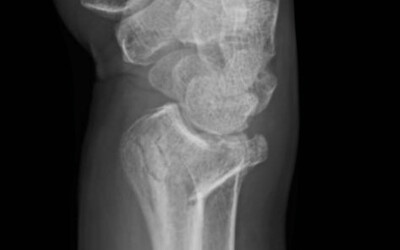

The wrist fracture. Colles fracture.

Created:15-07-2012 || Updated: 28-11-2020